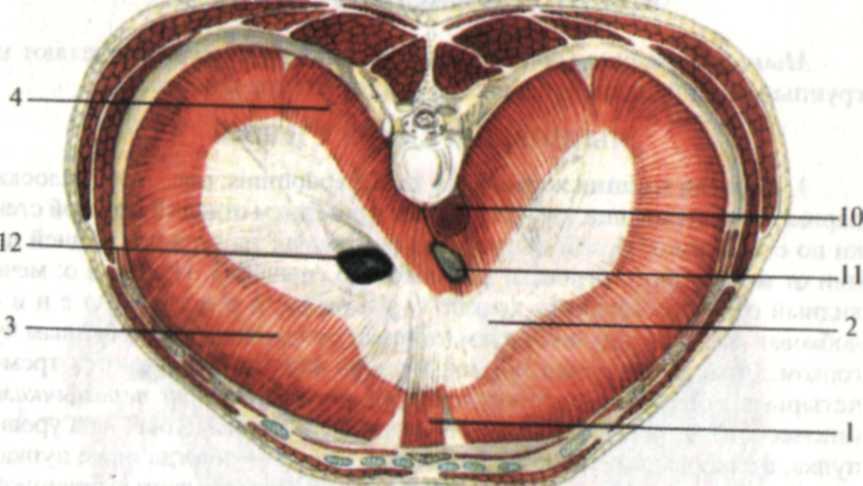

Анатомия диафрагмы и треугольника Бохдалека

Раздел: Визуальный дайджест